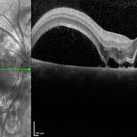

Preeclampsia in a 30-Year-Old - OCT - RE

Nov 25 2015 by Roy Schwartz, MD

A 30-year-old presented with central scotoma and blurred vision a day following C-section for preeclampsia.

Photographer: Galit Yair Pur

Condition/keywords: blurred vision, central scotoma, preeclampsia